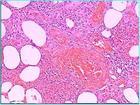

2 .病理診斷:皮膚結節活檢,其組織病理學改變是診斷的主要依據,它可分為三期:

( 1 )第一期(急性炎症期):在小葉內脂肪組織變性壞死,有中性粒細胞、淋巴細胞和組織細胞浸潤,部分伴有血管炎改變。

( 2 )第二期(吞噬期):在變性壞死的脂肪組織中有大量巨噬細胞浸潤,吞噬變性的脂肪細胞,形成具有特徵性的 " 泡沫細胞 " 。

( 3 )第三期(纖維化期):泡沫細胞大量減少或消失,被纖維母細胞取代;炎症反應被纖維組織取代,最後形成纖維化。